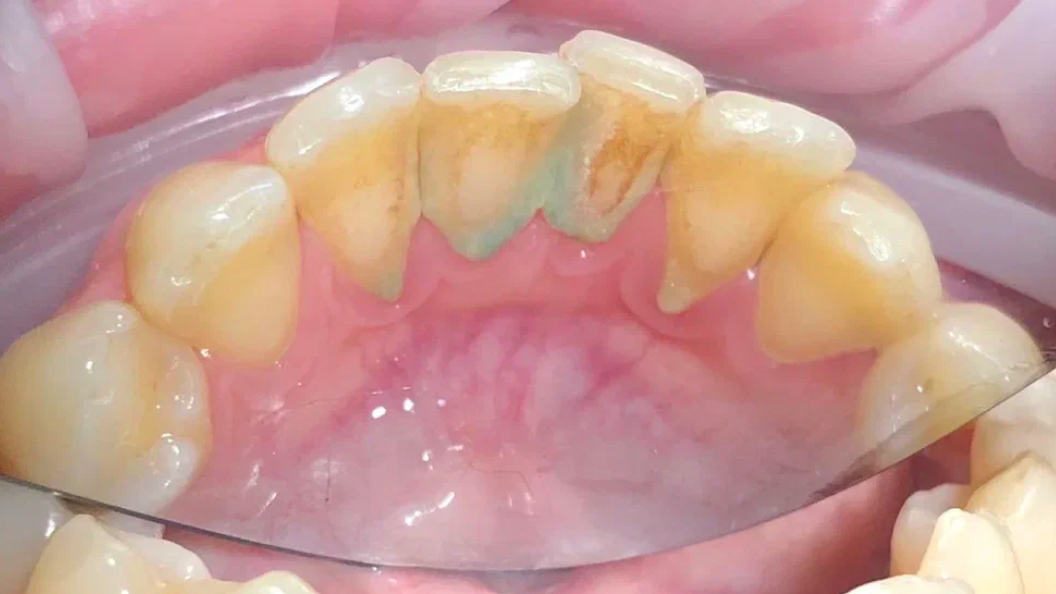

До и после лечения

В «Стоматологию Комфорта» обратился пациент с жалобами на наличие зубных отложений, а также кровоточивость дёсен во время чистки зубов. Врач Луцюк Наталья Владимировна провела осмотр и диагностировала хронический катаральный генерализованный гингивит. Было принято решение о проведении профессиональной гигиены полости рта с целью снятия минерализованных зубных отложений ультразвуком и удаления пигментированного налета пескоструйным аппаратом, а также последующей полировкой щеткой с пастой SuperPolish.

В ходе лечения проведены следующие работы:

- снятие минерализованных зубных отложений ультразвуком;

- удаление пигментированного налёта пескоструйным аппаратом;

- полировка зубов резиновой насадкой;

- финальная полировка пастой SuperPolish.